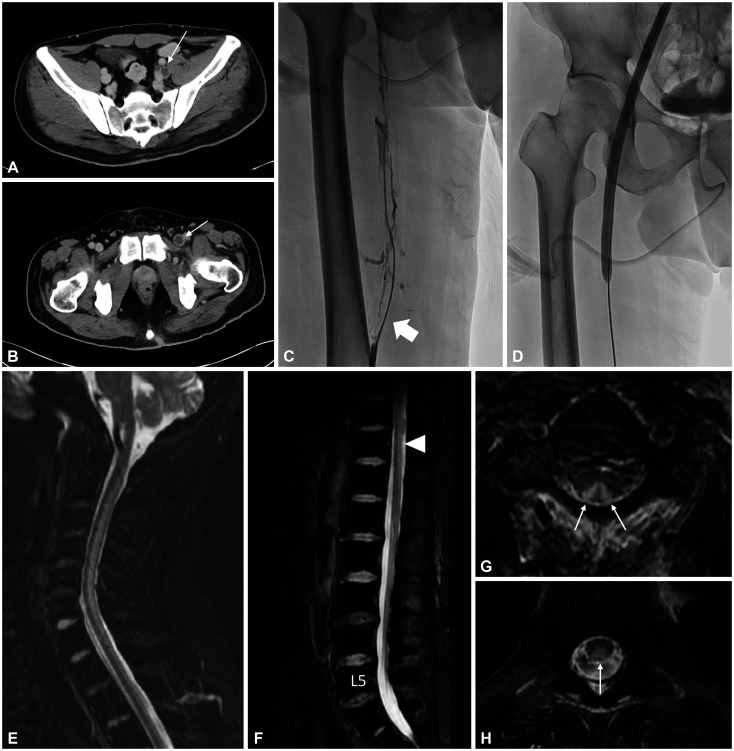

Concurrence of Subacute Combined Degeneration and Deep Vein Thrombosis After Chronic Nitrous Oxide Abuse.

慢性氧化亚氮滥用后并发亚急性合并变性和深静脉血栓形成。